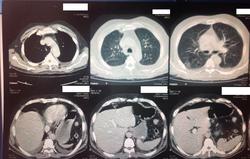

Пол пациента: Мужской пол Тип патологии: Злокачественное новообразование Область исследования: Грудная клетка и верхние дыхательные путиПищеварительная система Методы исследования: КТ к сожалению, ни анамнеза, ни жалоб у меня нет. только снимок. :( https://radiomed.ru/sites/default/files/styles/case_slider_image/public/user/19300/image_3_3.jpeg?itok=llGvHF8A https://radiomed.ru/sites/default/files/styles/case_slider_image/public/user/19300/image_1_3.jpeg?itok=m4fSrbr0 ID:33623 Пнд, 25/11/2013 - 16:58 #1 Петр Николаевич Не на сайте Был на сайте: 2 месяцев 2 недели назад Зарегистрирован: 15.03.2011 - 13:22 Публикации: 150 С чем разбираться? где снимки? Пнд, 25/11/2013 - 17:09 #2 Emchike Не на сайте Был на сайте: 10 лет 3 месяцев назад Зарегистрирован: 25.11.2013 - 14:06 Публикации: 4 анонимизированные изображенияПриложения: Пнд, 25/11/2013 - 17:12 #3 Helios Не на сайте Был на сайте: 1 год 2 недели назад Зарегистрирован: 06.08.2010 - 15:16 Публикации: 4417 Вот так-то лучше , но не совсем.Во-первых, жалобы, анамнез.Во-вторых, лучше дайкомы. Пнд, 25/11/2013 - 19:34 #4 Андрей Юрьевич Не на сайте Был на сайте: 2 недели 4 дня назад Зарегистрирован: 16.11.2008 - 22:16 Публикации: 18106 По тому, что видно - малый двусторонний гидроторакс. Андрей Юрьевич Пнд, 25/11/2013 - 19:50 #5 алкс Не на сайте Был на сайте: 10 лет 5 месяцев назад Зарегистрирован: 24.10.2012 - 22:55 Публикации: 2915 Андрей Юрьевич wrote: По тому, что видно - малый двусторонний гидроторакс. + Но это НЕ МРТ! Втр, 26/11/2013 - 00:38 #6 Emchike Не на сайте Был на сайте: 10 лет 3 месяцев назад Зарегистрирован: 25.11.2013 - 14:06 Публикации: 4 спасибо Втр, 26/11/2013 - 01:54 #7 Thirteenth Не на сайте Был на сайте: 11 лет 10 месяцев назад Зарегистрирован: 26.11.2013 - 01:51 Публикации: 3 Сдается мне, что в брюшной полости свободный возхдух - перфорация полого органа?

По тому, что видно - малый двусторонний гидроторакс.

Сдается мне, что в брюшной полости свободный возхдух - перфорация полого органа?